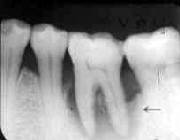

| FOp: 歯肉を切ってめくって歯石を取る  |

私は、重度以上のものしか手術の対象とはしていません。それは、手術する以上、抜髄して

連結固定してこそ初めて歯牙保存が可能だからです。如何に抜髄を推奨している私でも中等度

では抜髄をためらいます。歯周疾患進行に対しては抜髄が有効な抑制手段ではありますが、抜髄

には当然大きなディメリットをともないます。根管治療の不備から来る根尖病巣の誘発や歯根破折

など誰もが指摘するとおりです。

しかし、何もしないで放置した場合のナチュラルヒストリーは、重度で5年、それ以上では1年で

歯牙は自然脱落の運命をたどります。ところが、あえて積極的な治療を行った場合、重度では

10〜20年、それ以上の場合でも約10年機能させることが可能です。

| 48歳・男性 | 11年後 |

| 5」抜髄時・Fop+HAP施行 | 良く保ってるなぁ! |

| 同一症例 | 2年8ヵ月後 |

| 「6Fop+HAP施行 | 同じように治療したはずなのに… |